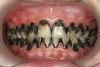

There are several advantages of using SDF in dental treatment. First, it showed an antimicrobial activity against mono-species, dual-species, and multi-species cariogenic biofilm.14-16 Silver ions are bactericidal metal cations that inhibit biofilm formation.17 Studies have indicated that silver interacts with sulfhydryl groups of proteins and DNA, thus altering hydrogen bonding and inhibiting respiratory processes, DNA unwinding, cell-wall synthesis, and cell division.18 At the macro level, these interactions affect bacterial killing and inhibit biofilm formation.17 Second, fluoride promotes caries lesion remineralization. Fluoride has been indicated to react with hydroxyapatite and generate calcium fluoride, which is a reservoir of fluoride, and facilitate further remineralization.19 An ex vivo study reported surface microhardness of the surface layer of the arrested caries after SDF applications was comparable with the unaffected sound dentin20 (Figure 1 and Figure 2). This is consistent with another study, in which a high remineralized zone was observed on the surface of arrested caries from exfoliated teeth with SDF treatment21 (Figure 3 and Figure 4). Third, its application procedures are simple and do not require injection or drilling, and the treatment does not involve expensive support infrastructure equipment such as piped water and electricity. The simplicity of the treatment is conducive to treating caries in apprehensive young children who may have intense dental fear, uncooperative patients with special needs, or elderly patients who have difficulty adapting to traditional dental care. It also allows trained workers to deliver the treatment to people who live in the area but who may not be able to easily access dental service.22 Patient compliance and satisfaction is often good when the patient is provided a clear explanation of the treatment outcome.23,24 Finally, the cost of SDF treatment is low and should be affordable in most communities.

The inherent disadvantage of SDF is that the caries lesions will be stained black after SDF application. SDF stops caries progression by forming a hard, blackened, impermeable layer on the tooth surface that is resistant to caries (Figure 5 through Figure 9). The authors’ clinical observations are that the darker the color, the more likely the caries arrested. Some patients may not be pleased with the esthetics of this treatment outcome; therefore, it is important to inform the patients and parents (for child patients) about this treatment outcome. Moreover, SDF can stain clothes and the skin of the body. Though it does not cause any pain or damage, an SDF stain on skin cannot be easily washed away. It takes around 7 days for it to disappear, and the stain on clothes is permanent.22